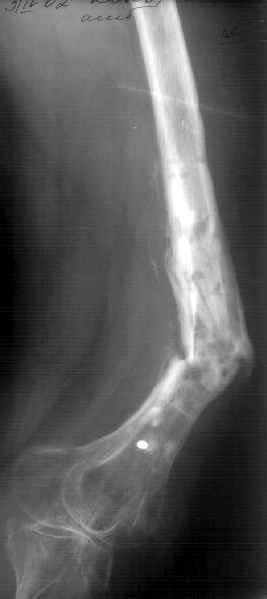

Не сформировалось у нас убежденности в целесообразности мобилизующей операции в один этап с остеосинтезом. Решили пойти по максимально щадящему пути. Первым этапом наложили аппарат. Снимок (см. приложение) сделан в положении максимально возможной коррекции оси, достигаемой одномоментно исправлением "об коленку" с ручным растягиванием колец сзади. Варус удалось убрать, а вот антекурвацию, от греха, лучше устраним дозированно, дней за 7-10. Потом планируем антеградный закрытый интрамедуллярный остесинтез. Буду признателен за отклик.

Кликните для загрузки файла 006.jpg

42KB (43081 bytes)